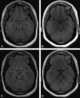

Diploic channel

The diploic veins are large, thin-walled valveless veins that channel in the diploĆ« between the inner and outer layers of the cortical bone in the skull. They are lined by a single layer of endothelium supported by elastic tissue. [Source: Wikipedia ]